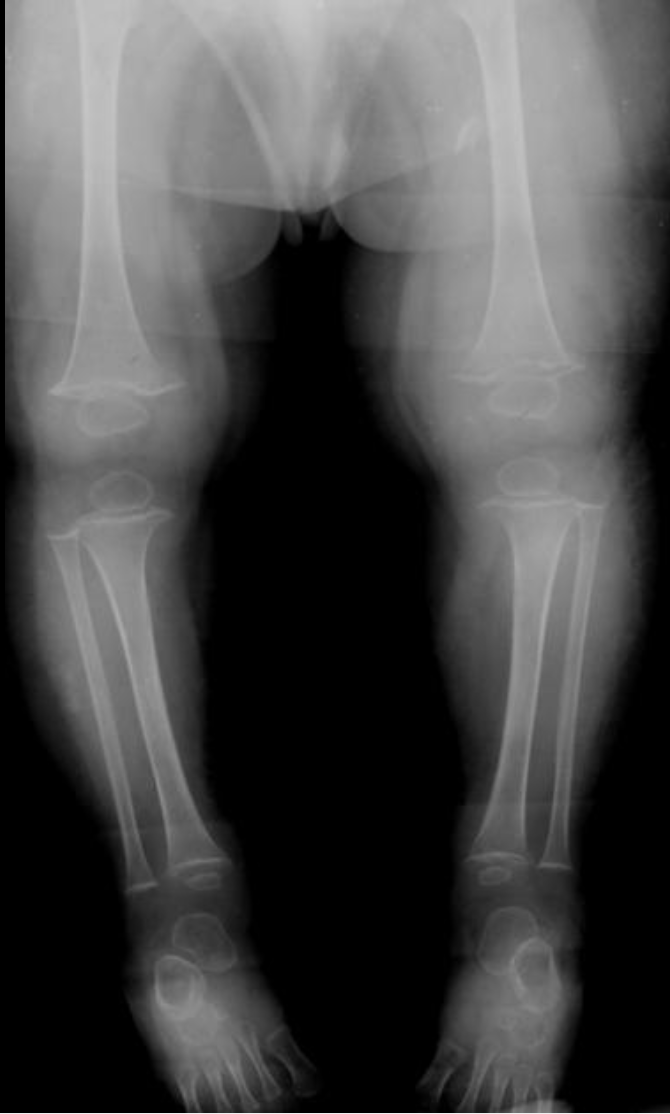

Blount Disease (Tibia vara)

• Stress on the posterior-medial physis results in suppression of growth at the proximal medial tibial physis

• Angulation is at the metaphysis NOT at the knee joint itself (although the knee joint is probably secondarily angled)

• Growth plate slants medially

• Metaphyseal-diaphyseal Angle > 11 deg

• Can be unilateral or bilateral

• Results in genu varum

• Compensatory hypertrophy of the medial meniscus

• Age 2 and 12 years old

• But never before age 2 years old

• Does not occur before walking

• Thought to occur from too much weight on immature leg

• Therefore typically does not occur before age 2

• Commonly bilateral

• RFs

• Fat kids

• Early walkers